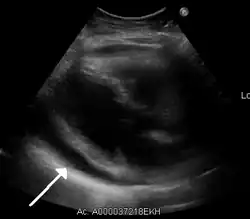

Pericarditis can progress to pericardial effusion and eventually cardiac tamponade. This can be seen in people who are experiencing the classic signs of pericarditis but then show signs of relief, and progress to show signs of cardiac tamponade which include decreased alertness and lethargy, pulsus paradoxus (decrease of at least 10 mmHg of the systolic blood pressure upon inspiration), low blood pressure (due to decreased cardiac index), (jugular vein distention from right sided heart failure and fluid overload), distant heart sounds on auscultation, and equilibration of all the diastolic blood pressures on cardiac catheterization due to the constriction of the pericardium by the fluid.

In such cases of cardiac tamponade, EKG or Holter monitor will then depict electrical alternans indicating wobbling of the heart in the fluid filled pericardium, and the capillary refill might decrease, as well as severe vascular collapse and altered mental status due to hypoperfusion of body organs by a heart that can not pump out blood effectively.

The diagnosis of tamponade can be confirmed with trans-thoracic echocardiography (TTE), which should show a large pericardial effusion and diastolic collapse of the right ventricle and right atrium. Chest X-ray usually shows an enlarged cardiac silhouette ("water bottle" appearance) and clear lungs. Pulmonary congestion is typically not seen because equalization of diastolic pressures constrains the pulmonary capillary wedge pressure to the intra-pericardial pressure (and all other diastolic pressures).